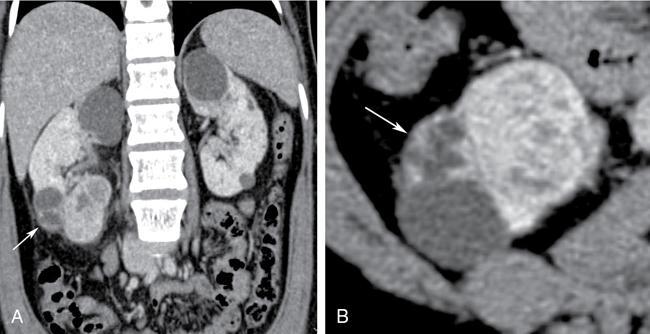

Bosniak category IV

- Imaging: Bosniak type IV cysts are characterized by the presence of enhancing soft tissue nodule (Fig. 10.12.1.7).

- Risk of malignancy: They are considered malignant until proven otherwise, with risk of malignancy being 95%–100%. Very small percentage can be benign, example being MEST.

- Recommendations: Surgical resection is recommended if feasible.